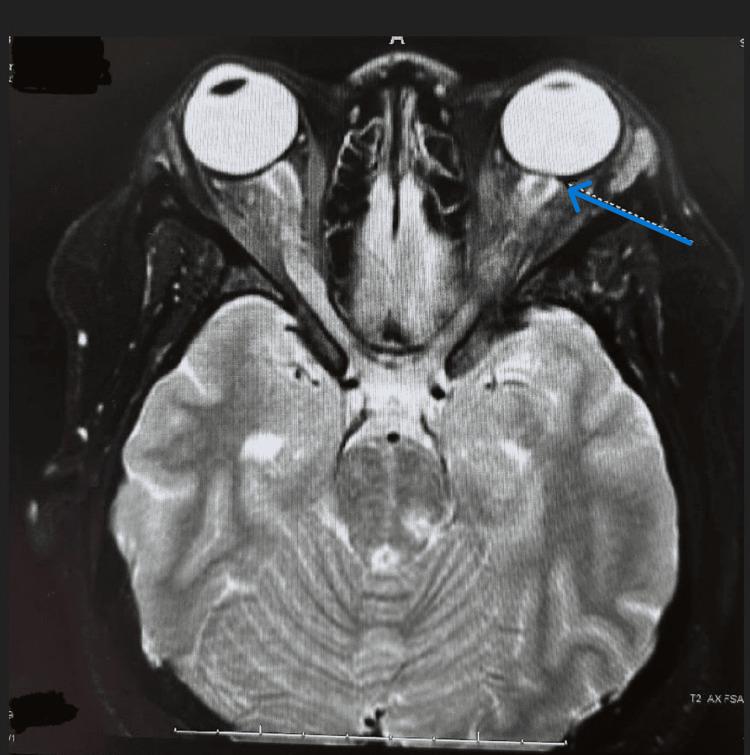

Idiopathic intracranial hypertension (IIH) is a clinical diagnosis made from the exclusion of other possible causes of increased intracranial pressure (ICP): cerebrospinal fluid (CSF) overflow obstruction, mass lesion, infection, or malignancies. IIH is a phenomenon with a rapid onset that most notably presents in obese women of childbearing age. We present the case of a 30-year-old African American woman with a past medical history of bipolar disorder who arrived at the emergency department (ED) with acute bilateral vision loss, two weeks of bilateral retro-orbital headache, painful eye movements, and progressive vision loss with a decrease in appetite. Management involved plasma exchange, high-dose steroids, consistent neurological and ophthalmic tests, and close observation and follow-up. One week after the most recent ED visit, the patient confirmed a significant improvement in vision. When diagnosing our patient with IIH, it was imperative to rule out myelinating oligodendrocyte glycoprotein antibody-associated disease (MOGAD), multiple sclerosis (MS), and other demyelinating diseases such as optic neuritis. Initial brain imaging using computed tomography (CT) without contrast showed no evidence of intracranial hemorrhage but demonstrated the presence of prominent sheath complexes, suggestive of optic neuritis, and a slightly small pituitary gland height for a patient who is 30 years of age. Further testing with a CT venogram (CTV) and a magnetic resonance imaging (MRI) of the head and neck confirmed demyelination. The patient's lumbar puncture continuously revealed a normal opening pressure during her hospital stay. This case presentation will highlight and compare the current literature regarding the clinical presentation and management of idiopathic intracranial hypertension.

特发性颅内高压(IIH)是一种通过排除颅内压(ICP)升高的其他可能原因而做出的临床诊断:脑脊液(CSF)溢流阻塞、占位性病变、感染或恶性肿瘤。IIH是一种起病迅速的现象,最常见于育龄肥胖女性。我们报告一例30岁非裔美国女性病例,她有双相情感障碍病史,因急性双侧视力丧失、双侧眶后头痛两周、眼球运动疼痛、视力进行性下降伴食欲减退而到急诊科就诊。治疗包括血浆置换、大剂量类固醇、持续的神经和眼科检查以及密切观察和随访。在最近一次急诊科就诊一周后,患者确认视力有显著改善。在诊断我们的患者患有IIH时,必须排除髓鞘少突胶质细胞糖蛋白抗体相关疾病(MOGAD)、多发性硬化症(MS)和其他脱髓鞘疾病,如视神经炎。最初使用无对比剂的计算机断层扫描(CT)进行脑部成像,未发现颅内出血迹象,但显示存在明显的鞘复合体,提示视神经炎,且对于一名30岁的患者来说,垂体高度略小。进一步通过CT静脉造影(CTV)以及头部和颈部的磁共振成像(MRI)检查确认了脱髓鞘。患者住院期间腰椎穿刺持续显示初压正常。本病例报告将突出并比较当前关于特发性颅内高压临床表现和治疗的文献。